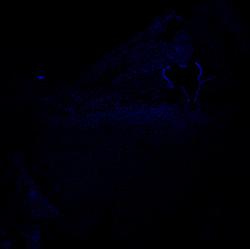

An anatomical analysis of the developing human midbrain from 6 post-conceptional weeks (PCW) to 22 PCW reveals increased tissue complexity, characterized by the emergence of dopaminergic nuclei, as highlighted by immunofluorescence analysis for tyrosine hydroxylase (TH).

DAPI

6PCW human midbrain